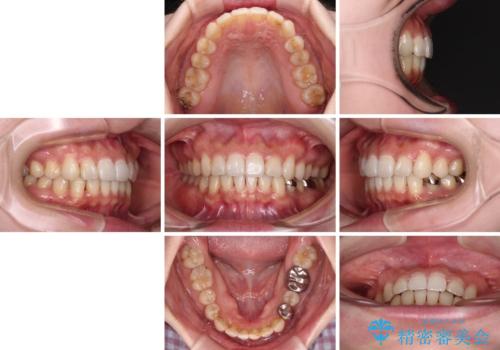

インビザラインを用いて、前歯の叢生を解消するとともに、深い咬み合わせ(ディープバイト)を改善していくこととしました。

奥歯を後方に直立させることで深い咬み合わせを改善を図り、隠れていた下顎前歯が見えるほどになりました。